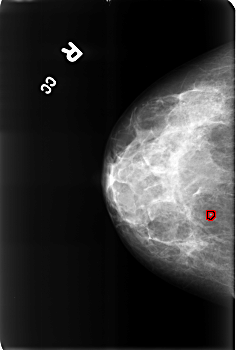

B_3169_1.RIGHT_CC

RIGHT_CC LINES 4544 PIXELS_PER_LINE 3072 BITS_PER_PIXEL 12 RESOLUTION 50 OVERLAY

FILE: B_3169_1.RIGHT_CC.OVERLAY

TOTAL_ABNORMALITIES 1

ABNORMALITY 1

LESION_TYPE CALCIFICATION TYPE LUCENT_CENTER DISTRIBUTION N/A

ASSESSMENT 2

SUBTLETY 3

PATHOLOGY BENIGN_WITHOUT_CALLBACK

TOTAL_OUTLINES 1

BOUNDARY